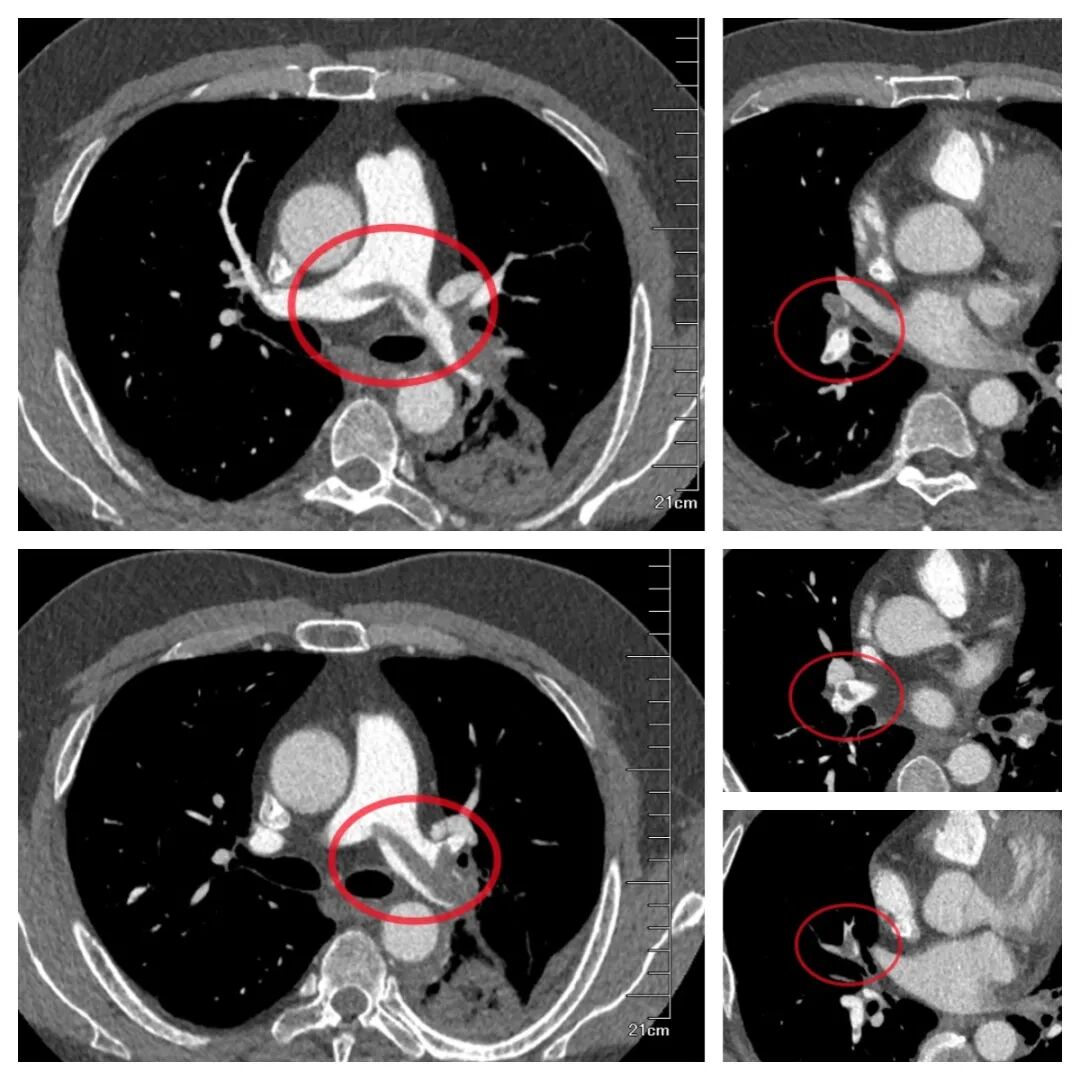

为明确诊断,医生迅速为小李安排下肢血管彩超检查,结果证实了担忧:右侧小腿肌肉内静脉附壁血栓,右下肢深静脉血栓形成,且血栓头端部分游离,随时可能脱落引发致命性肺栓塞。进一步的血气分析显示,小李存在严重低氧血症,强化肺动脉 CTA更提示双肺已出现大量血栓,救治刻不容缓!

△强化肺动脉 CTA提示双肺已出现大量血栓